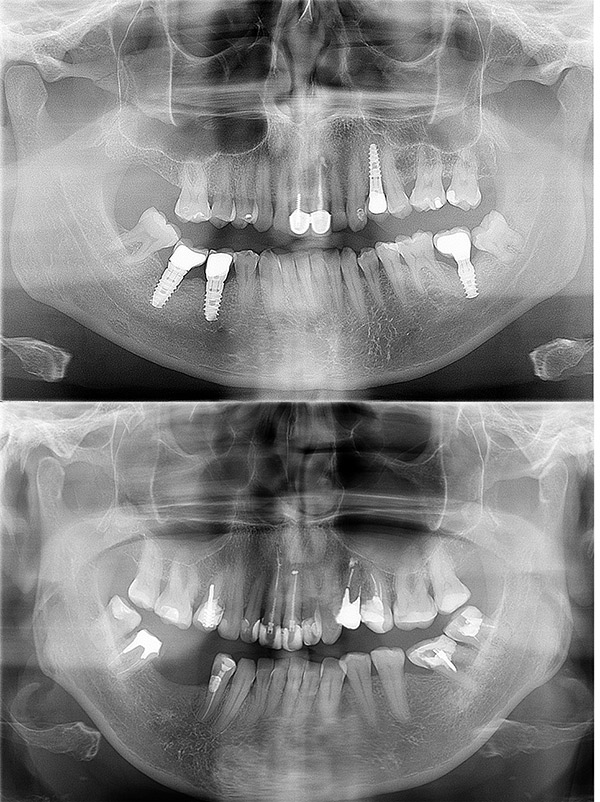

Radiografía panorámica u ortopantomografía

Es la más usual. Este tipo de radiografía da una imagen completa de toda la boca, por lo que es muy útil para tener una visión general. Es la que suele hacerse cuando el paciente viene a nuestra clínica dental en Valencia por primera vez, y también cuando viene anualmente a los sucesivos controles y mantenimientos. Se realiza con una máquina especial que rota alrededor de la cabeza. Se utiliza para planificar cualquier tipo de tratamiento: ortodoncia, implantes dentales, planear cirugías de extracciones de muelas del juicio, entre otros casos.